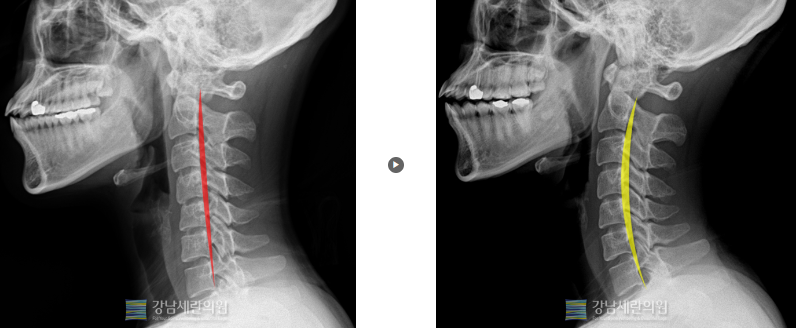

일자목 교정전 ▶ 일자목 30회(3개월) 치료 후

일자목 교정 전 ▶ 일자목 30회(3개월) 치료 후